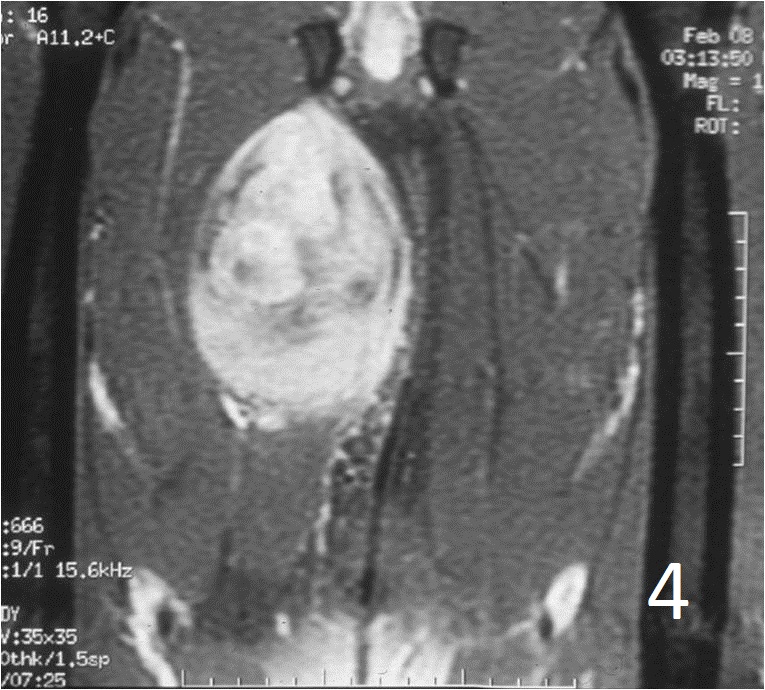

• Well defined heterogenous mass on T2W (Fig. 4, 9)

• On gadolinium, viable areas of tumor enhance, while areas of significant necrosis and hemorrhage do not enhance (Fig. 6).

Fig. 2-4: An MRI of the thigh shows a mass in the medial compartment that is isointense to muscle on T1W images (Fig. 2) and heterogeneous on T2W (Fig. 3). Sagittal T1W post contrast with gadolinium demonstrates enhancement of the tumor (Fig. 4).